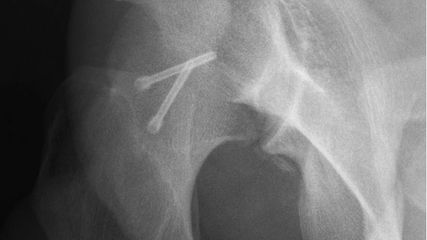

Abb. 7: Postoperatives a.-p. Hüftübersichtsröntgen. Eine kleine knöcherne Frakturimpression und eine chondrale Stufe von weniger als 2mm sind verblieben

Abb. 8: Postoperatives a.-p. Hüftübersichtsröntgen. Die Hüftkopfzirkumferenz ist wiederhergestellt

Alle Hüftkopffrakturen sollten einer frühzeitigen und frühfunktionellen Behandlung zugeführt werden. Die Hüftbeugung sollte in den ersten 6 Wochen auf 60° limitiert werden, um so einer dorsalen Instabilität oder sekundären Luxation vorzubeugen. Nach einer osteosynthetischen Versorgung empfehlen wir eine Teilbelastung mit Sohlenkontakt bis maximal 20kg Körpergewicht für die ersten 6 Wochen postoperativ unter der Verwendung von 2 Unterarmstützkrücken (Abb. 7–9). Ferner empfehlen wir zur Prophylaxe heterotoper Ossifikationen die orale Medikation mit nichtsteroidalen Antirheumatika.